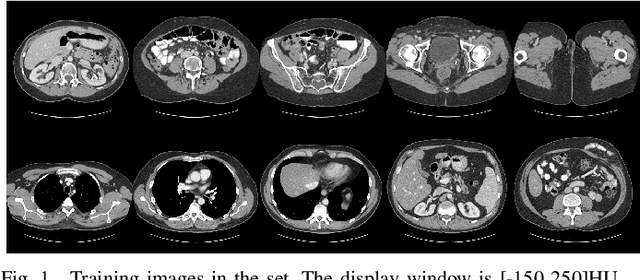

Abstract:Due to the presence of metallic implants, the imaging quality of computed tomography (CT) would be heavily degraded. With the rapid development of deep learning, several network models have been proposed for metal artifact reduction (MAR). Since the dual-domain MAR methods can leverage the hybrid information from both sinogram and image domains, they have significantly improved the performance compared to single-domain methods. However,current dual-domain methods usually operate on both domains in a specific order, which implicitly imposes a certain priority prior into MAR and may ignore the latent information interaction between both domains. To address this problem, in this paper, we propose a novel interactive dualdomain parallel network for CT MAR, dubbed as IDOLNet. Different from existing dual-domain methods, the proposed IDOL-Net is composed of two modules. The disentanglement module is utilized to generate high-quality prior sinogram and image as the complementary inputs. The follow-up refinement module consists of two parallel and interactive branches that simultaneously operate on image and sinogram domain, fully exploiting the latent information interaction between both domains. The simulated and clinical results demonstrate that the proposed IDOL-Net outperforms several state-of-the-art models in both qualitative and quantitative aspects.

Abstract:Metal implants can heavily attenuate X-rays in computed tomography (CT) scans, leading to severe artifacts in reconstructed images, which significantly jeopardize image quality and negatively impact subsequent diagnoses and treatment planning. With the rapid development of deep learning in the field of medical imaging, several network models have been proposed for metal artifact reduction (MAR) in CT. Despite the encouraging results achieved by these methods, there is still much room to further improve performance. In this paper, a novel Dual-domain Adaptive-scaling Non-local network (DAN-Net) for MAR. We correct the corrupted sinogram using adaptive scaling first to preserve more tissue and bone details as a more informative input. Then, an end-to-end dual-domain network is adopted to successively process the sinogram and its corresponding reconstructed image generated by the analytical reconstruction layer. In addition, to better suppress the existing artifacts and restrain the potential secondary artifacts caused by inaccurate results of the sinogram-domain network, a novel residual sinogram learning strategy and nonlocal module are leveraged in the proposed network model. In the experiments, the proposed DAN-Net demonstrates performance competitive with several state-of-the-art MAR methods in both qualitative and quantitative aspects.

Abstract:Compressed sensing (CS) computed tomography has been proven to be important for several clinical applications, such as sparse-view computed tomography (CT), digital tomosynthesis and interior tomography. Traditional compressed sensing focuses on the design of handcrafted prior regularizers, which are usually image-dependent and time-consuming. Inspired by recently proposed deep learning-based CT reconstruction models, we extend the state-of-the-art LEARN model to a dual-domain version, dubbed LEARN++. Different from existing iteration unrolling methods, which only involve projection data in the data consistency layer, the proposed LEARN++ model integrates two parallel and interactive subnetworks to perform image restoration and sinogram inpainting operations on both the image and projection domains simultaneously, which can fully explore the latent relations between projection data and reconstructed images. The experimental results demonstrate that the proposed LEARN++ model achieves competitive qualitative and quantitative results compared to several state-of-the-art methods in terms of both artifact reduction and detail preservation.